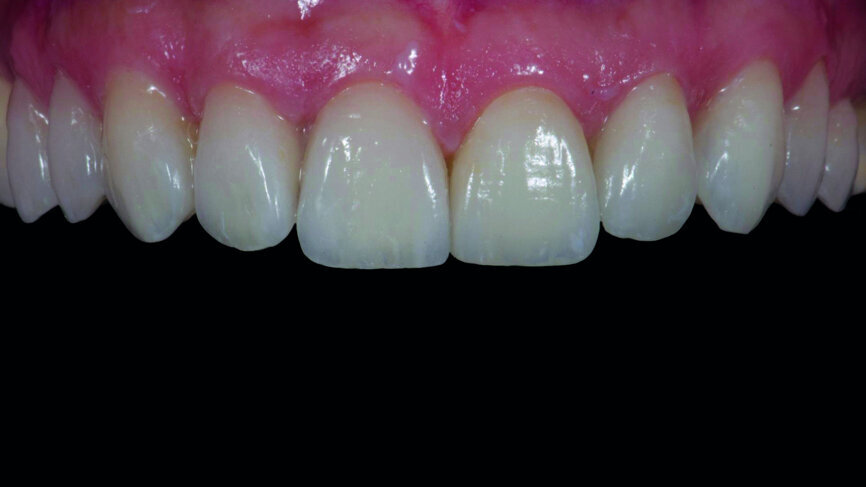

Fig. 15a: Feldspathic veneers with try-in paste.

Fig. 15b: CAD/CAM veneers with try-in paste.

Fig. 15c: First quadrant feldspathic veneers and second quadrant CAD/CAM veneers simultaneously with try-in paste.

Provisionalisation was executed digitally, using Telio CAD (Ivoclar Vivadent) in the Wieland Select CNC milling machine. The design was performed with the 3Shape DentalDesigner 2015 software (Figs. 12a & b). Two sets of final restorations were fabricated. The set of feldspathic veneers was fabricated on a stone model using IPS Style (Ivoclar Vivadent), while IPS Empress CAD Multi (Ivoclar Vivadent) was used for the digitalset (Figs. 13 & 14). Both sets were examined intraorally with a try-in paste to compare the optical properties of the feldspathic and the CAD/CAM veneers (Figs. 15a–c).